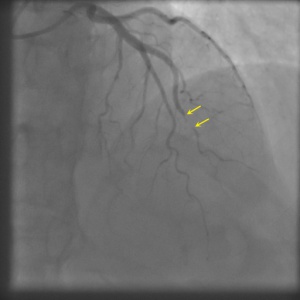

Type 1

Projection angle: 14 RAO, 35 CRA. Type 1 SCAD is seen in OM2.